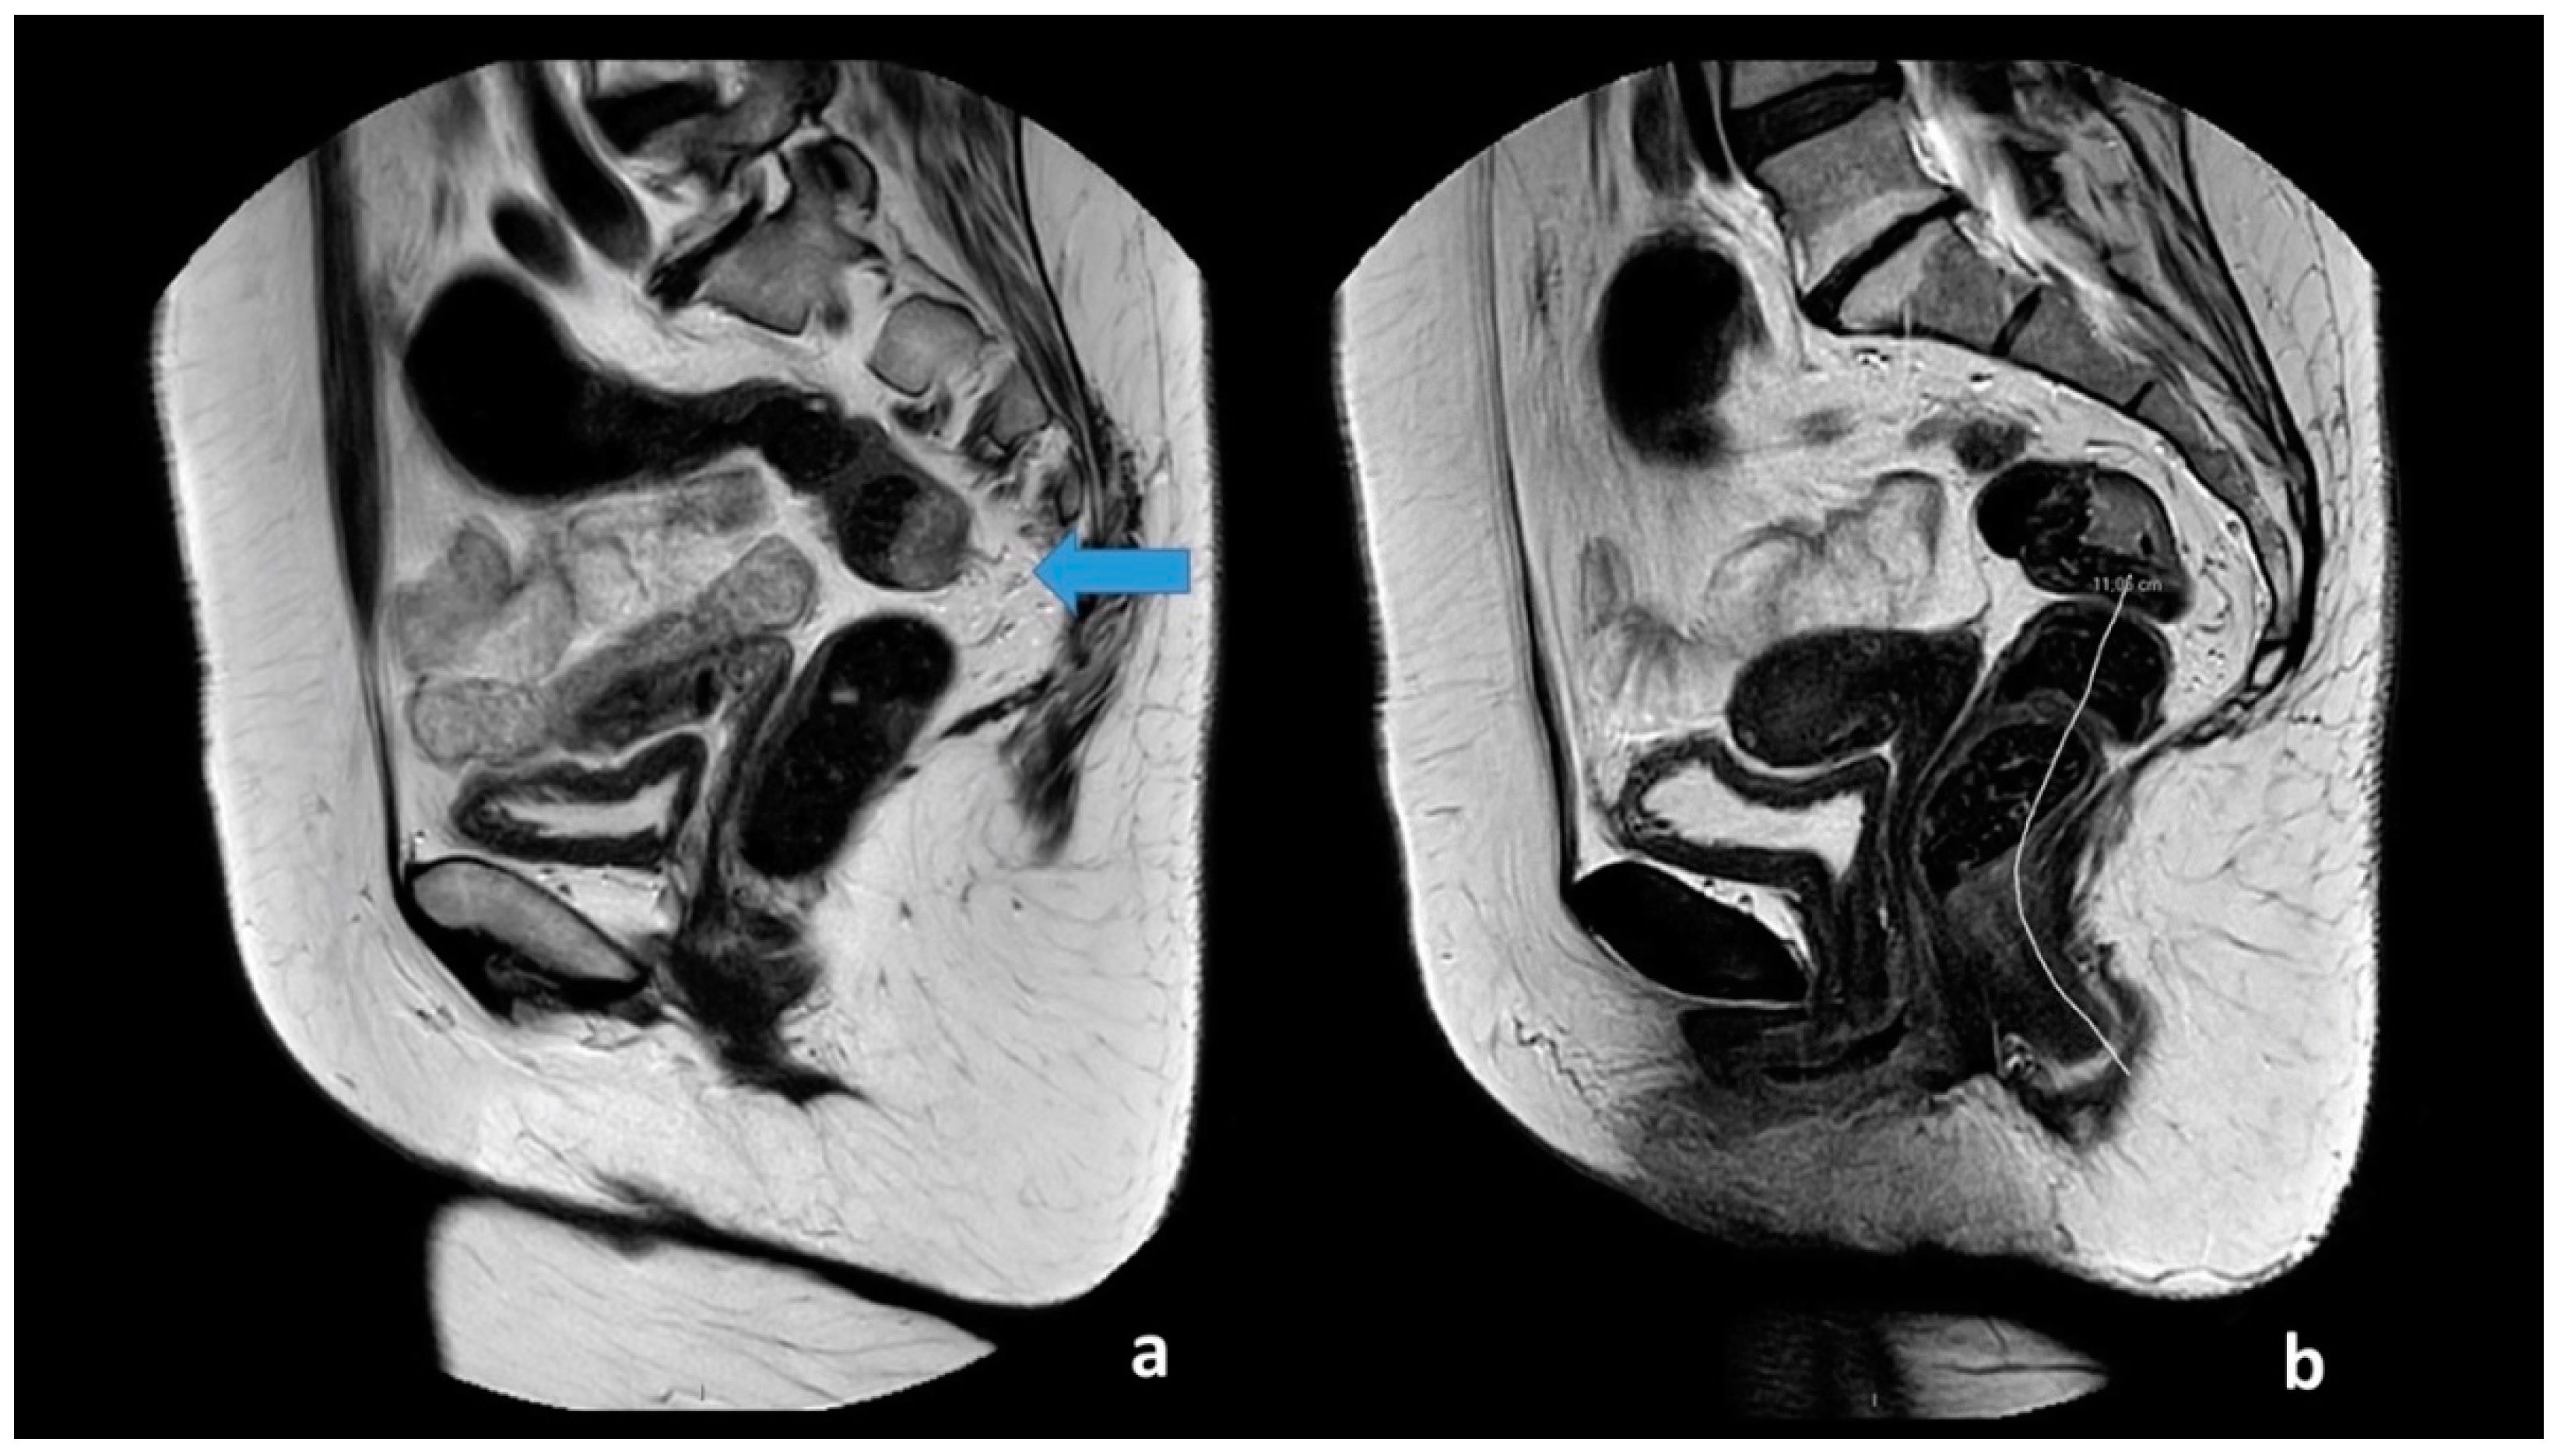

All images had a quality check by one of two authors (M.R.V.P and S.R.R). The two observers received a basic instruction on how to perform the assessment of the anal verge and takeoff, defined as the point from which the sigmoid sweeps horizontally away from the sacrum. The observers used the sigmoid blood vessels insertion as an adjunct in the determination of the location. The two observes measured the distance from the anal verge to the sigmoid takeoff using a curved digital ruler. The measurement of the anal verge and takeoff is visualized in Figure 1. The observers were blinded to the patient history, diagnosis, and prior image investigations. T2W-weighted MRI images with 3 mm slice thickness were used to perform the measurements.

Figure 1. Sagittal T2-weighted images from a 65-year-old female patient with a T1 tumor located at the posterior wall just above the sigmoid takeoff. The arrow indicates the sigmoid take-off from which the sigmoid sweeps horizontally away from the sacrum and with the sigmoid blood vessels insertion (a). The takeoff and the lower border of the tumor is located 11 cm above the anal verge (b).